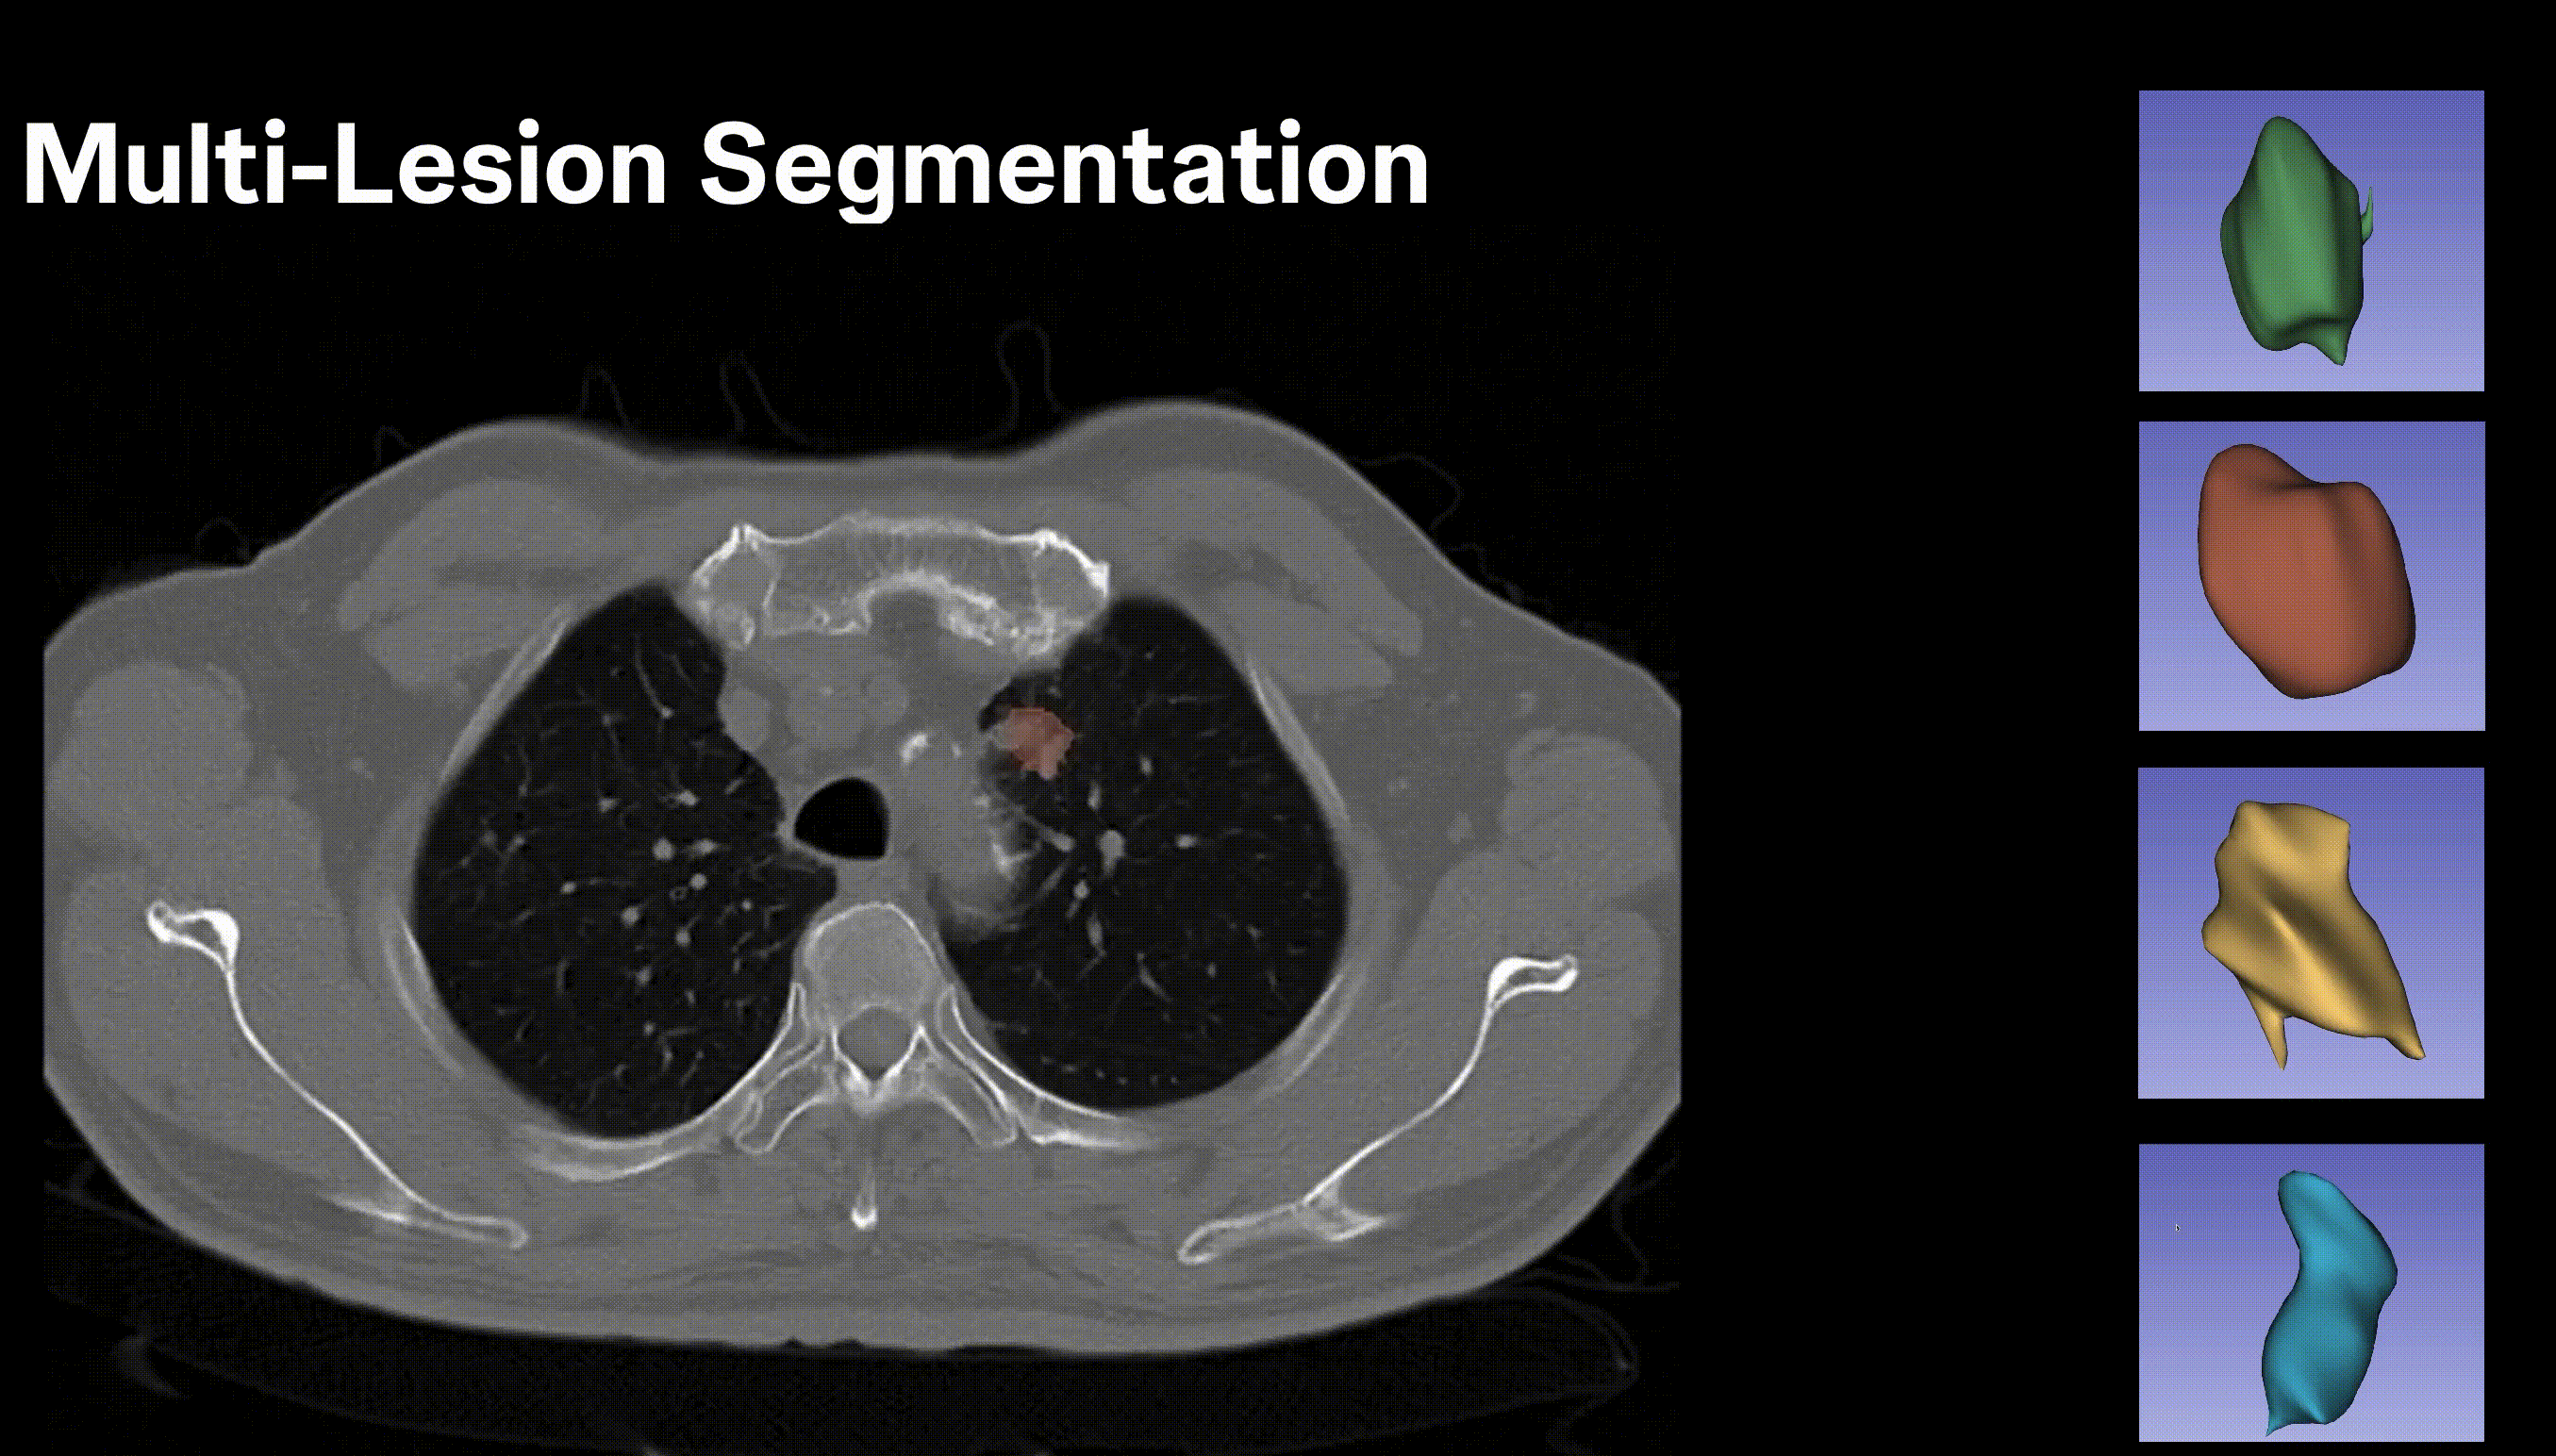

I’m a Senior AI Scientist at Johnson & Johnson. I have 8+ years of experience designing and deploying scalable, high-impact AI solutions in computer vision, multi-modal learning, and foundation models. I specialize in self-supervised learning, model compression, and multi-modal AI, driving state-of-the-art advancements in medical imaging and AI-powered drug discovery. I finished my PhD from Chester F. Carlson Center for Imaging Science at Rochester Institute of Technology (RIT), Rochester, NY under the direction of my advisor, Dr. Cristian Linte, funded by NSF and NIH grants. My PhD thesis focused on deep learning architectures for segmentation in medical imaging. I worked at Philips Research designing an optimized object detection framework for COVID-19 lung ultrasound, and at IBM Research on deep neural network pruning/optimization for explainable AI.

• Semantic & instance segmentation for medical imaging (2D/3D)

Deep Learning, AI & Computer Vision

3D CT Segmentation SAM / MedSAM Vision Transformers Self / Semi-Supervised